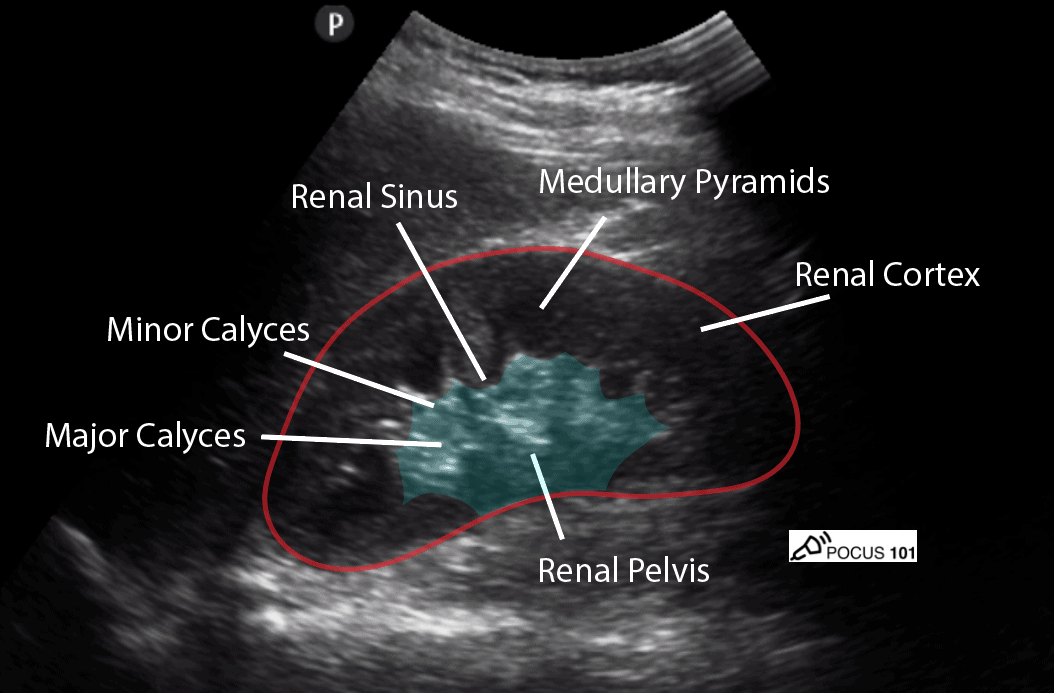

Figure 2. Sonographic appearance of normal kidney [5]

5. Identify components of the kidney (see Figure 2).

Hydronephrosis can be graded based on the amount of swelling in the kidney. As the grading increases, the structures in the kidney are more swollen due to the backflow. Grade 1 hydronephrosis is when the pelvis is dilated. As it progresses to grade 2, dilation also involves the major calyces. For grade 3 hydronephrosis, there is also dilation of the minor calyx. Grade 4 is indicated by cortical thinning. Determining the specific grade is less important than identifying hydronephrosis and recognizing that it’s a continuum, starting from more central structures and progressing outward as the severity increases [5].

Pitfalls

Hydronephrosis can commonly be confused with the medullary pyramids of the kidneys, as well as cysts or vascular prominence/malformation. Pyramids and renal cysts are distinct structures and tend to be more peripherally located compared to hydronephrosis which starts centrally. Vasculature can be differentiated from hydronephrosis with color doppler [5-7].